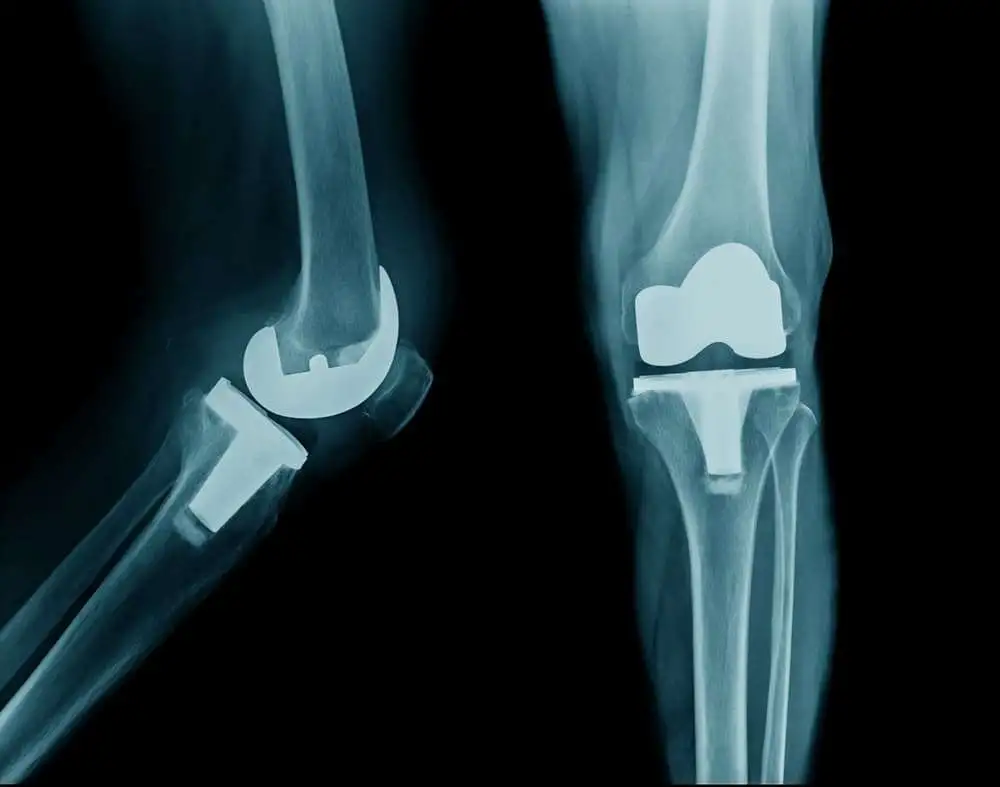

d-and l-Aspartate (Asp) were quantified for whole cartilage, collagen and non-collagenous components of cartilage obtained at the time of joint replacement. We computed the Asp racemization ratio (Asp-RR = d/d + l Asp), reflecting the proportion of old to total protein, for each component.

Compared with hip OA, knee OA collagen fibrils (P < 0.0001), collagen (P = 0.007), and non-collagenous proteins (P = 0.0003) had significantly lower age-adjusted mean Asp-RRs consistent with elevated protein synthesis in knee OA. Knee OA collagen had a mean hydroxyproline/proline (H/P) ratio of 1.2 consistent with the presence of type III collagen whereas hip OA collagen had a mean H/P ratio of 0.99 consistent with type II collagen. Based on Asp-RR, the relative age was significantly different in knee and hip OA (P < 0.0005); on average OA knees were estimated to be 30yrs ‘younger’, and OA hips 10yrs ‘older’ than non-OA.